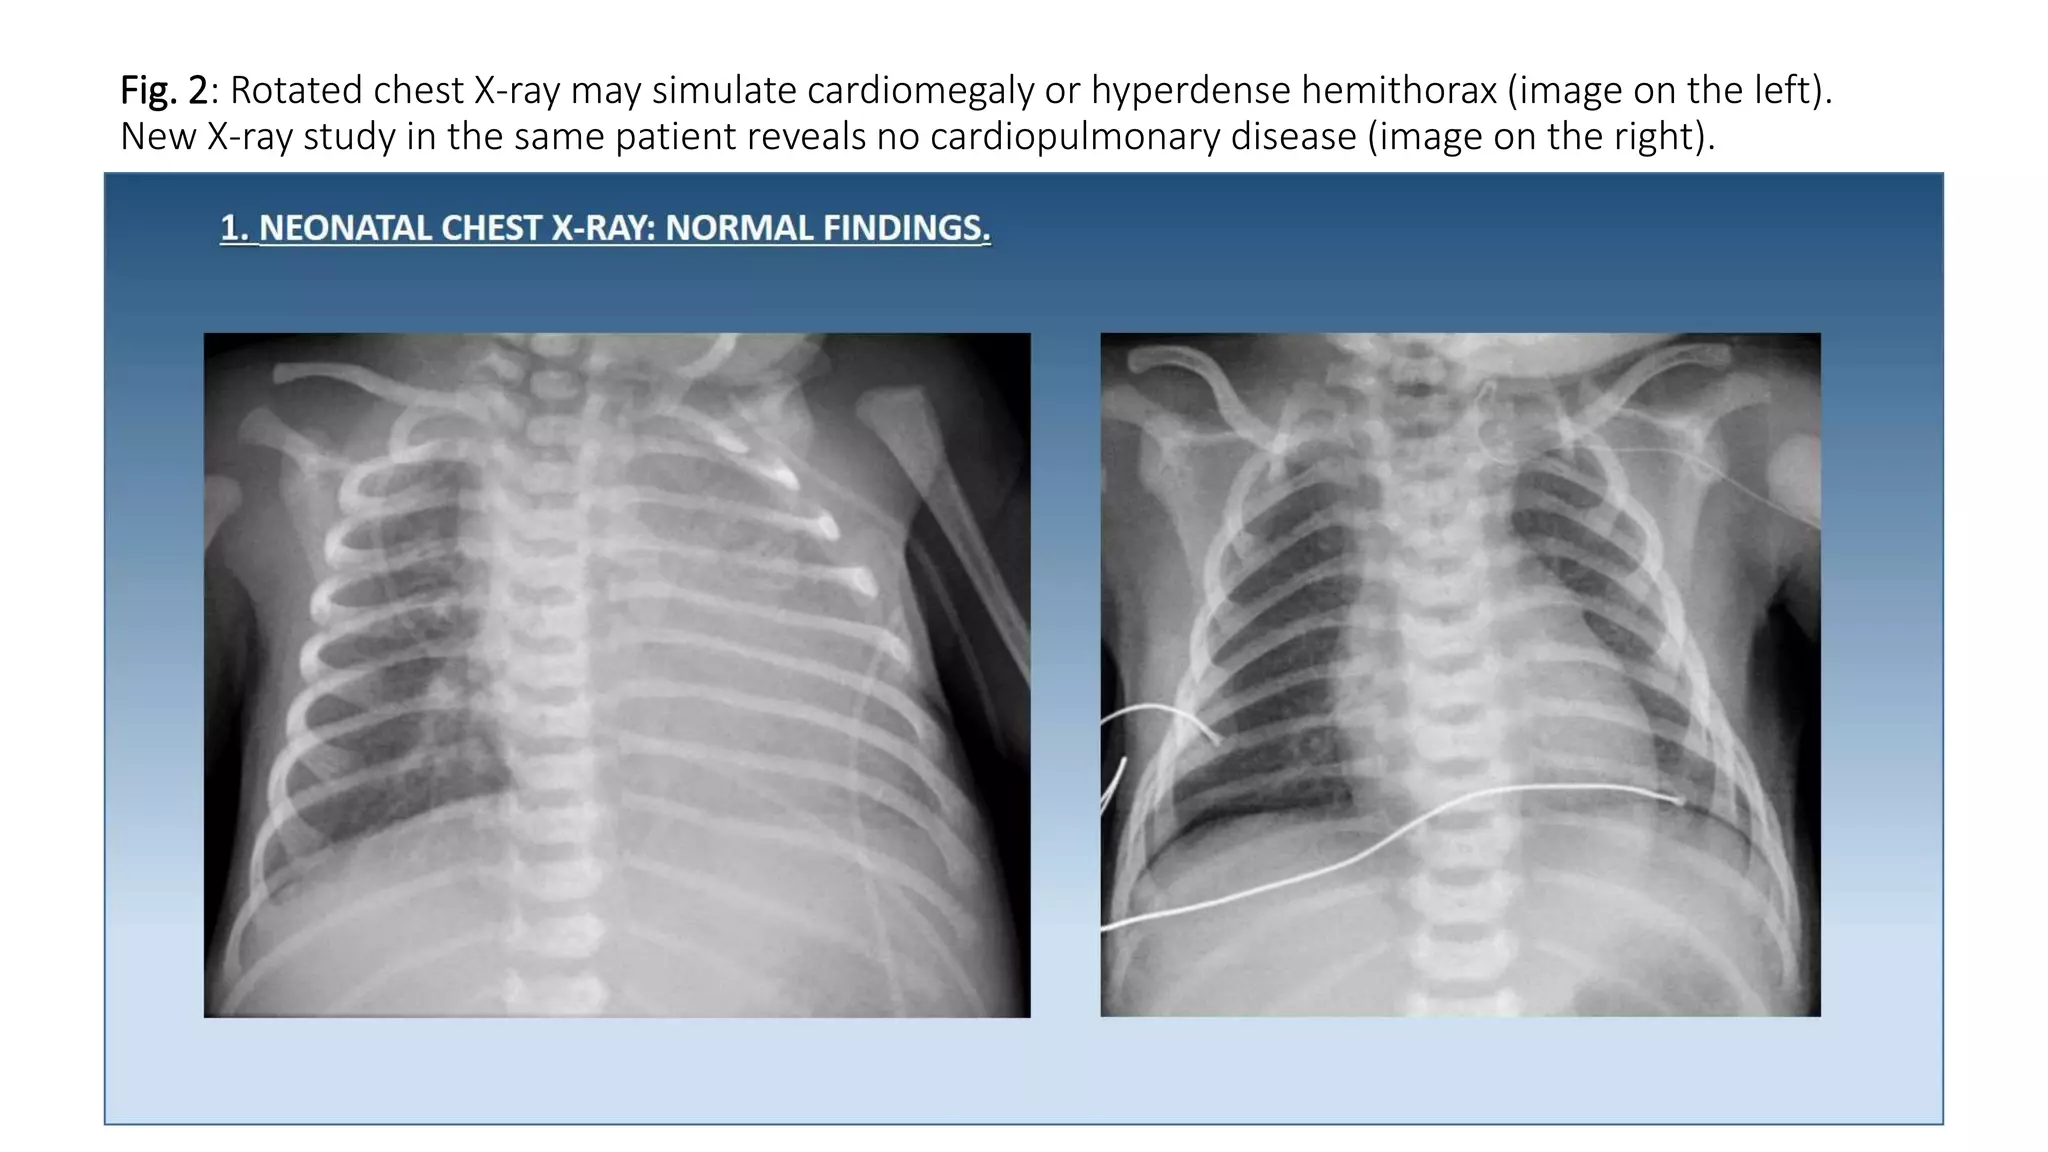

This document provides an overview of neonatal chest x-rays, including when they should and should not be performed, what a normal x-ray looks like, common positions of tubes and catheters, and common causes of respiratory distress in neonates. It discusses the appearance of a normal chest x-ray as well as conditions like respiratory distress syndrome, transient tachypnea of the newborn, meconium aspiration syndrome, and pneumonia. Surgical conditions like diaphragmatic hernia and esophageal atresia are also reviewed.